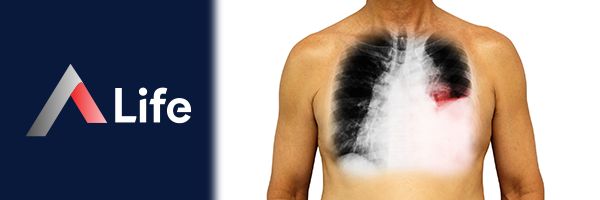

Plevral efüzyon, akciğerleri ve göğüs boşluğunu çevreleyen ince zar tabakası olan plevra arasında sıvı birikmesi durumudur. Plevra, iki katmandan oluşur: akciğerleri kaplayan visseral plevra ve göğüs boşluğunu kaplayan parietal plevra. Normalde bu iki zar arasında az miktarda sıvı bulunur ve bu sıvı, akciğerlerin nefes alırken ve verirken göğüs boşluğu içinde rahatça hareket etmesini sağlar.

Plevral efüzyonda, plevra arasındaki sıvı miktarı artar ve bu da akciğerlere baskı yaparak nefes darlığına ve diğer solunum problemlerine yol açabilir.